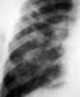

Honeycomb lung

Honeycombing or "honeycomb lung" is the radiological appearance seen with widespread fibrosis and is defined by the presence of small cystic spaces with irregularly thickened walls composed of fibrous tissue. Dilated and thickened terminal and respiratory bronchioles produce cystic airspaces, giving honeycomb appearance on chest x-ray. [Source: Wikipedia ]